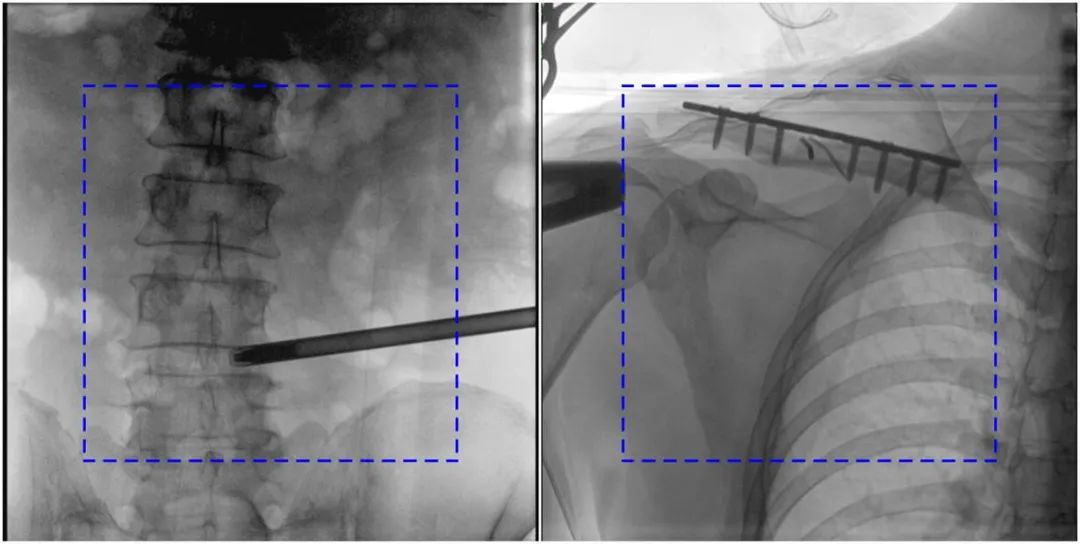

PLX119C临床图像与传统图像对比

注:蓝色虚线内为传统21CM×21CM平板的成像区域。